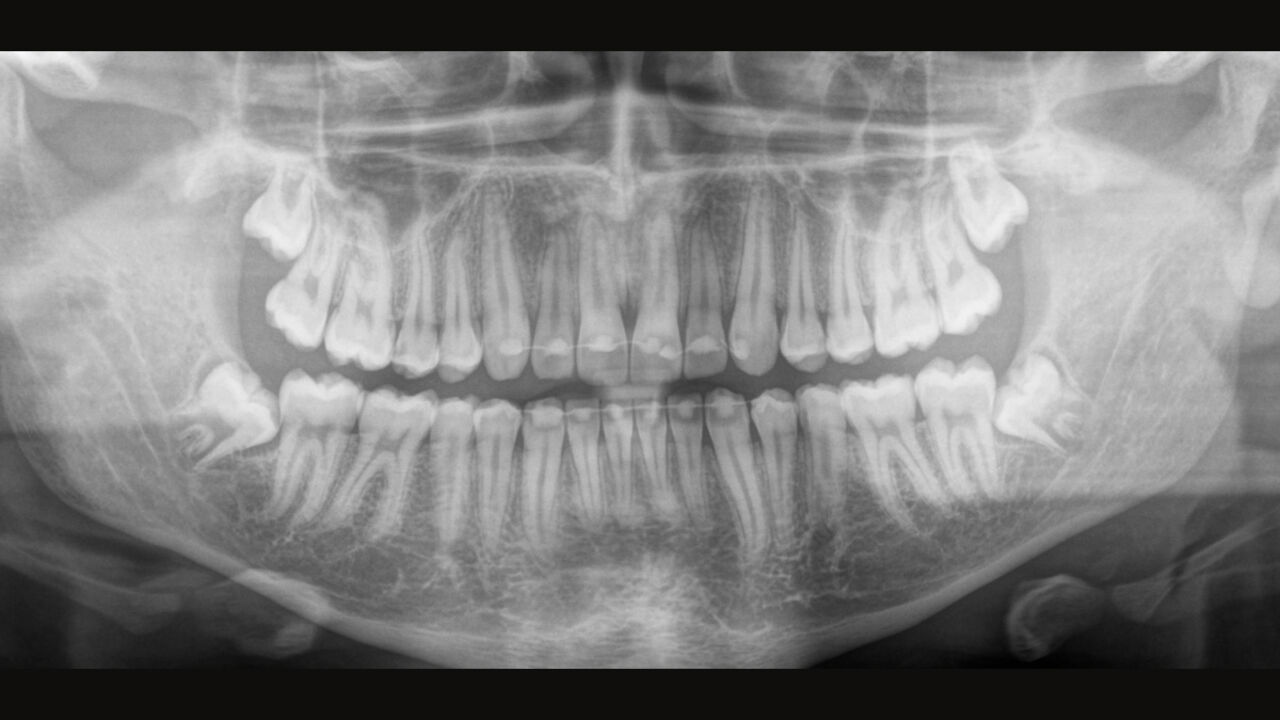

Para obtener imágenes panorámicas excepcionales con alta nitidez. Puede elegir un brazo cefalométrico derecho o izquierdo opcional, que puede reacondicionarse en cualquier momento

El sensor de conversión directa (Direct Conversion Sensor, DCS) ha revolucionado el estándar de la imagen panorámica. Las imágenes radiológicas se convierten directamente en señales eléctricas. Por lo tanto, no hay pérdida de señal debido a conversión de la luz, como es el caso de los sistemas convencionales. El resultado: imágenes con un alto nivel de nitidez y contraste, incluso con una dosis de radiación extremadamente baja. Para obtener información de diagnóstico precisa a fin de apoyar el tratamiento objetivo.

La imagen a continuación muestra una radiografía panorámica con y sin tecnología DCS. Usando la flecha, arrastre el control a través de la imagen para ver la diferencia que el sensor de conversión directa hace con la calidad de la imagen y las posibilidades de diagnóstico.